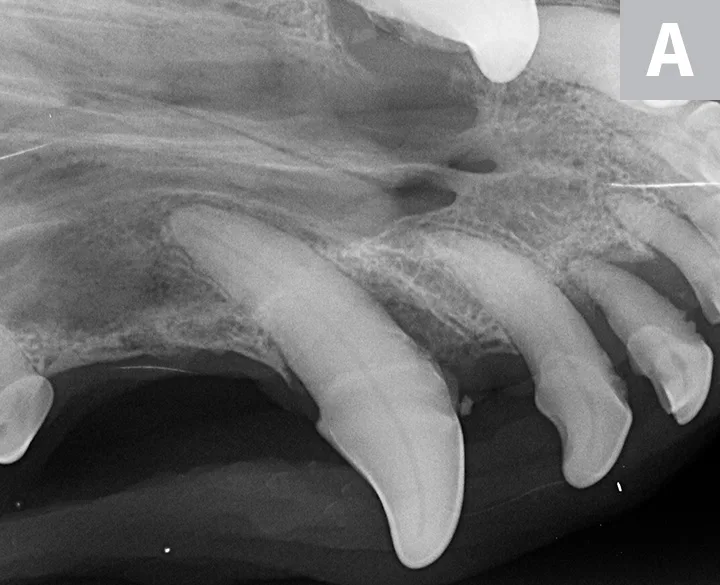

Three dental radiographs.

Figure 2

Dental radiographs of the right (A) and left (B) maxillary canine teeth (lateral views) and the rostral maxillae (C; occlusal view) confirmed mild horizontal and severe vertical bone loss at the mesial aspect of both maxillary canine teeth. Moderate to severe horizontal bone loss at the right maxillary first incisor tooth (blue arrow) and total loss of attachment with inflammatory root resorption at the right maxillary second incisor tooth (yellow arrow) were present. The remaining maxillary incisor teeth were affected by mild horizontal bone loss. Although the occlusal view of the rostral maxillae is slightly asymmetric, osteolysis was evident in the area of the left palatine fissure (red arrow). Mild horizontal bone loss was diagnosed at several other teeth. In addition, retained root tip of the left maxillary (presumably) first premolar tooth (white arrow) was identified.